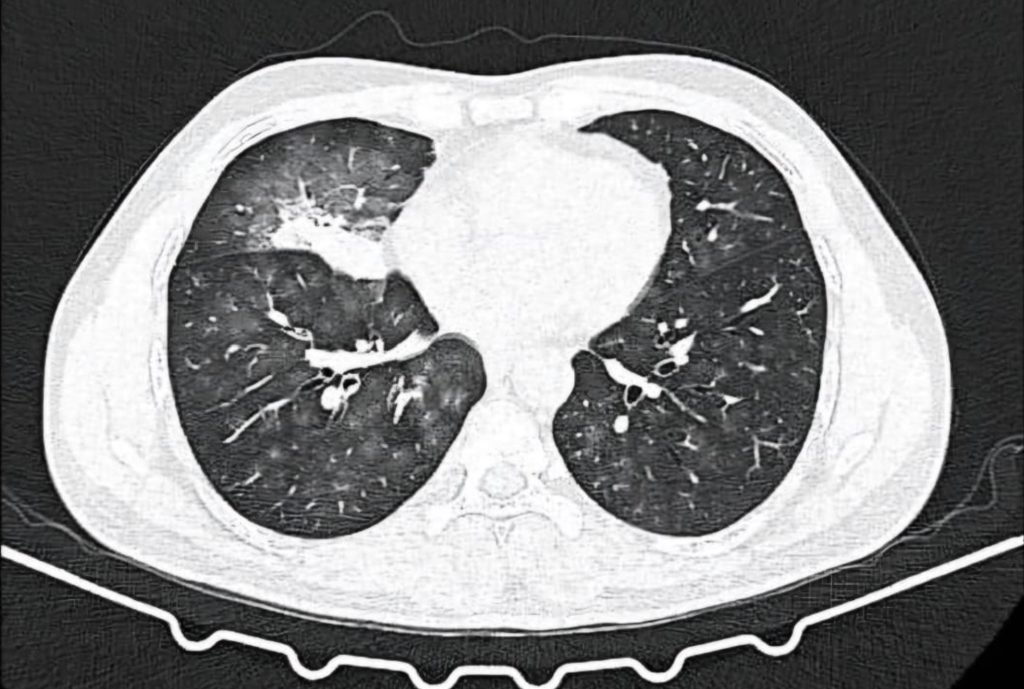

CT Thoracic angiography:

- Collapse consolidation of right middle lobe with ground glass opacities in bilateral lung fields.

- Hypertrophied bronchial collateral supplying area of consolidation.